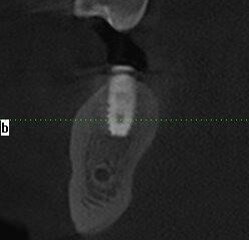

Wykonano CBCT, z którego wynikało, iż pacjent ma chorobę przyzębia. Zakwalifikowano wszystkie 10 zębów żuchwy do ekstrakcji. Zaplanowano zaopatrzenie pacjenta 8 implantami ICX oraz 5 implantami tymczasowymi Alpha Bio w celu wykonania pracy protetycznej tymczasowej bez obciążenia implantów docelowych ze względu na brak kontroli nad pacjentem w okresie wgajania implantów (zdjęcie CBCT oraz wewnątrzustne pacjenta). Za pomocą komputerowego systemu nawigacyjnego 3D został zaprojektowany szablon przytwierdzany 3 pinami do kości żuchwy w celu jego stabilizacji.